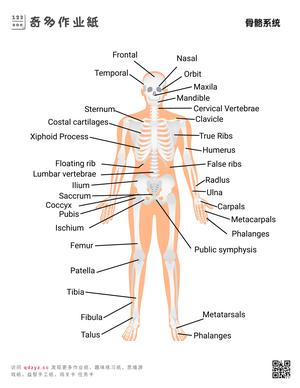

奇多作业纸生活常识系列提供幼儿通识教育资源,涵盖天气与季节认知、人体部位图解、交通安全常识、动植物百科、日常卫生习惯等核心主题。内容设计参照《3-6岁儿童学习与发展指南》科学领域目标,通过图片认知、分类游戏和问答练习三种形式实现多维度学习。常识教育是幼儿建立世界认知框架的基础环节,也是幼小衔接面试的常考内容。所有资源下载打印,适合3-7岁儿童使用。

- 掌握基本身体部位名称和功能

包括:交通安全规则(红灯停绿灯行)、卫生习惯(饭前洗手)、四季变化特征、基本身体部位名称、常见动植物辨认、简单的天气现象识别等。

通过图片闪卡、问答游戏和场景模拟三种方式效果最佳。例如用天气卡片认识晴天、雨天;用人体图谱学习身体部位;用交通标志卡开展安全教育。